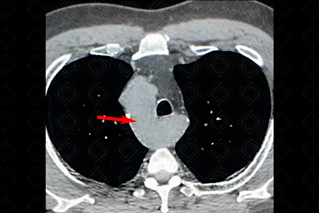

Texto alternativo para a imagem Créditos: Dra. Elazir Mota - Rio de Janeiro/RJ

Descrição da figura: Tomografia computadorizada do tórax evidenciando arco aórtico à direita (seta vermelha).

Arco aórtico à direita: Trata-se de uma das variantes do arco aórtico, rara (ocorre em aproximadamente 0,1% da população) e caracteriza-se pelo curso do arco aórtico à direita da traqueia. Diferentes tipos podem ser encontrados, dependendo dos ramos supra-aórticos, sendo os mais comuns: arco aórtico à direita com os ramos supra-aórticos dispostos em espelho e arco aórtico direito com subclávia esquerda aberrante. Essa variação anatômica pode estar associada a uma variedade de defeitos cardíacos congênitos.

• Tomografia computadorizada ou ressonância magnética do tórax: P ermitem visualização direta do arco aórtico à direita (f igura acima).